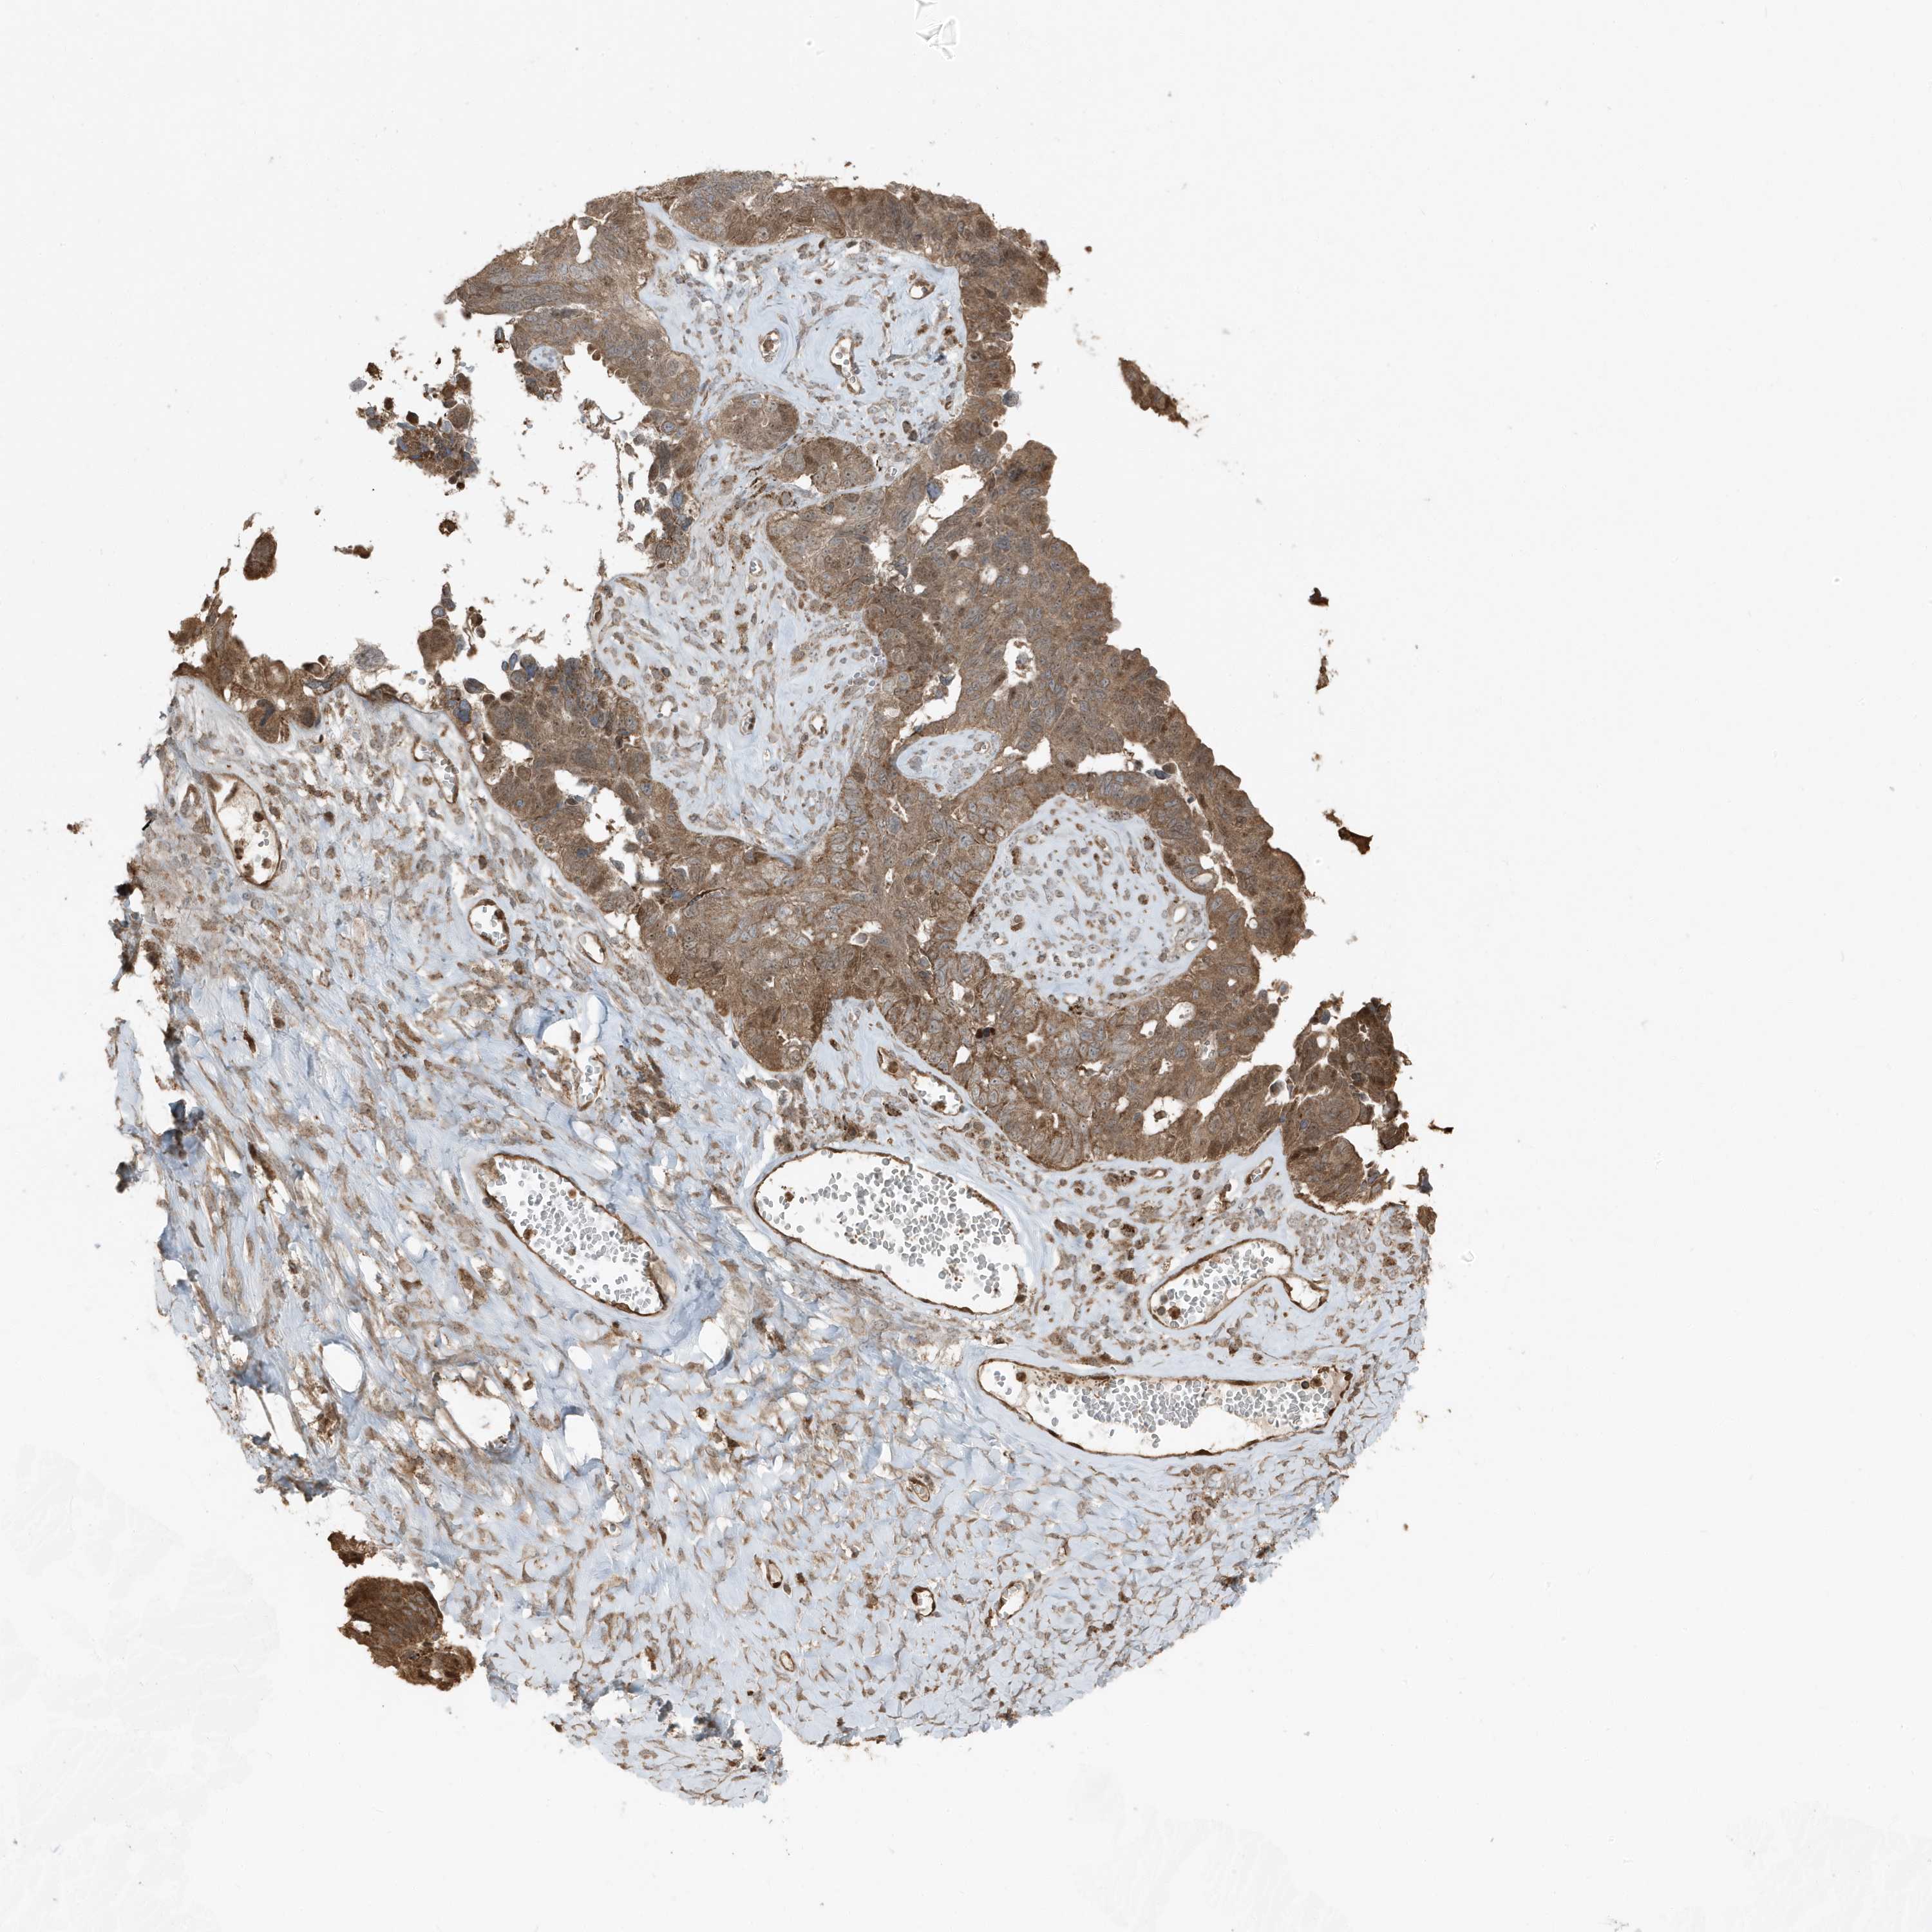

OVARIAN CANCER - Protein expressioni

A mouse-over function shows sample information and annotation data. Click on an image to view it in a full screen mode. Samples can be filtered based on level of antibody staining by selecting one or several of the following categories: high, medium, low and not detected. The assay and annotation is described here.

Note that samples used for immunohistochemistry by the Human Protein Atlas do not correspond to samples in the TCGA dataset.

Antibody stainingi

Antibody staining in the annotated cell types in the current human tissue is reported as not detected, low, medium, or high, based on conventional immunohistochemistry profiling in selected tissues. This score is based on the combination of the staining intensity and fraction of stained cells.

Each image is clickable and will lead to virtual microscopy that enables deeper exploration of all samples and also displays staining intensity scores, fraction scores and subcellular localization as well as patient and tissue information for each sample.

Antibody HPA035258

Staining

High

Medium

Low

Not detected

Intensity

Strong

Moderate

Weak

Negative

Quantity

>75%

75%-25%

<25%

None

Location

Nuclear

Cytoplasmic/membranous

Cytoplasmic/membranous,nuclear

Cystadenocarcinoma, serous, NOS

Carcinoma, endometroid

Cystadenocarcinoma, mucinous, NOS

Carcinoma, NOS